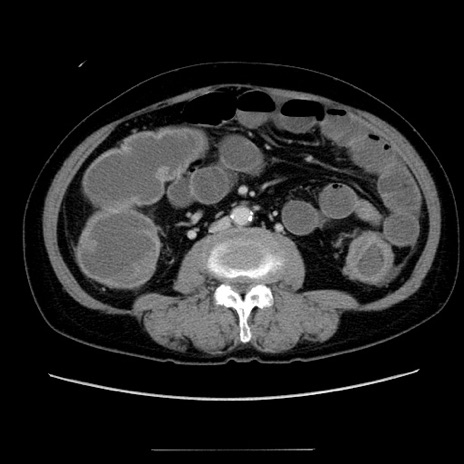

症例5(横断像)

【症例】70歳代女性

【主訴】お腹が張る

【現病歴】1週間くらい前から腹部膨満の自覚あり。昨日夜から増悪したため、本日救急外来受診。

【身体所見】意識清明、BT 36.5℃、BP 165/106mmHg、HR 80bpm、SpO2 98%、腹部:膨満、軟、自発痛・圧痛なし、触診にて不快感あり、腸蠕動音:減弱

【データ】WBC 12600、CRP 1.04